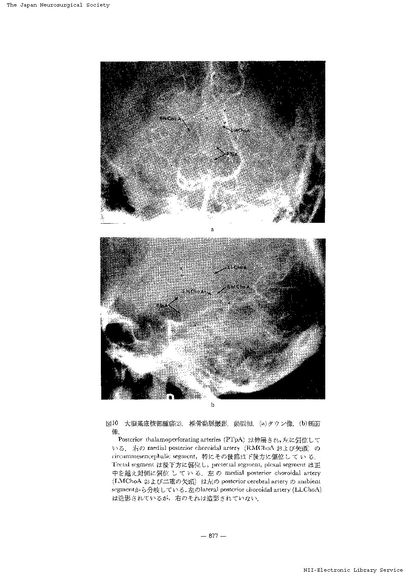

第3脳室近傍腫瘍の神経放射線診断-脳血管撮影を中心に- III 主に第3脳室の側方に発育する腫瘍(2)